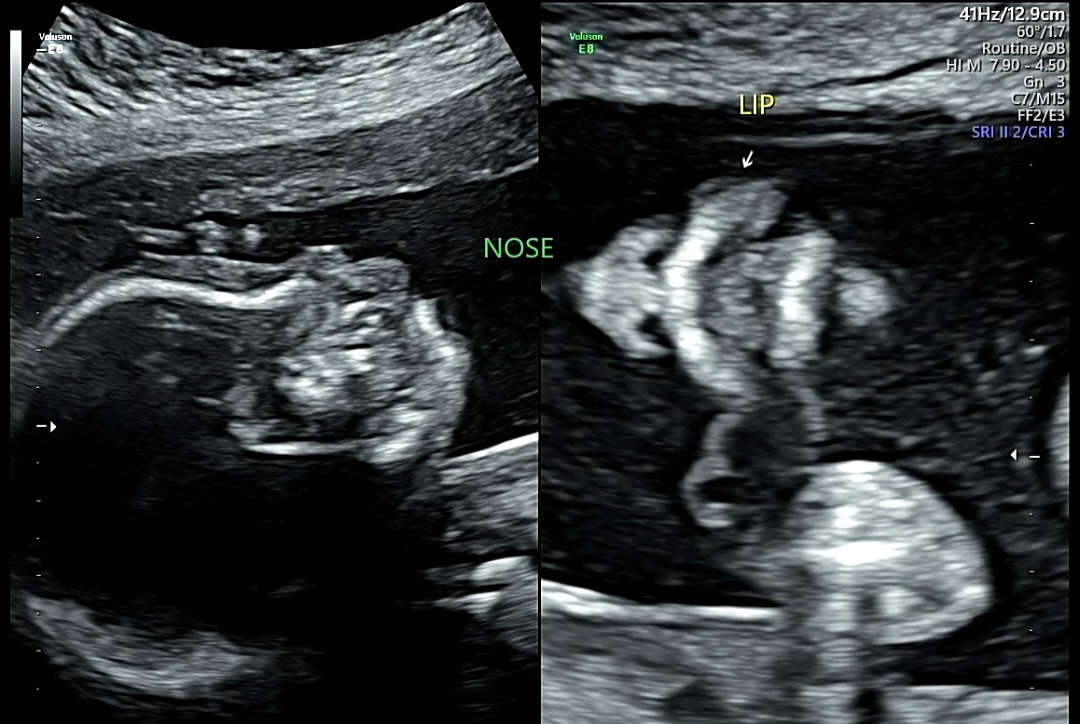

7. 얼굴 발달 확인

1) NOSE(코)/LIP(입술)